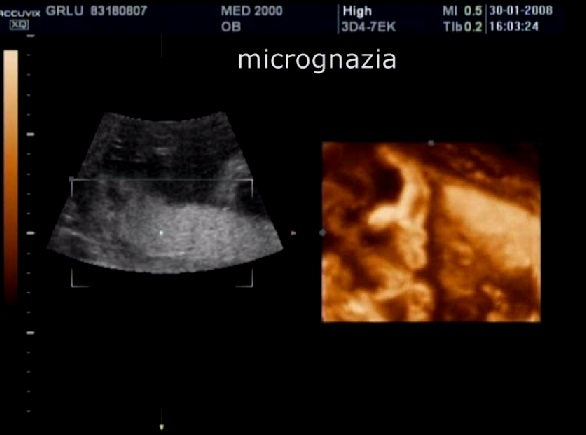

2. micro-retrognazia